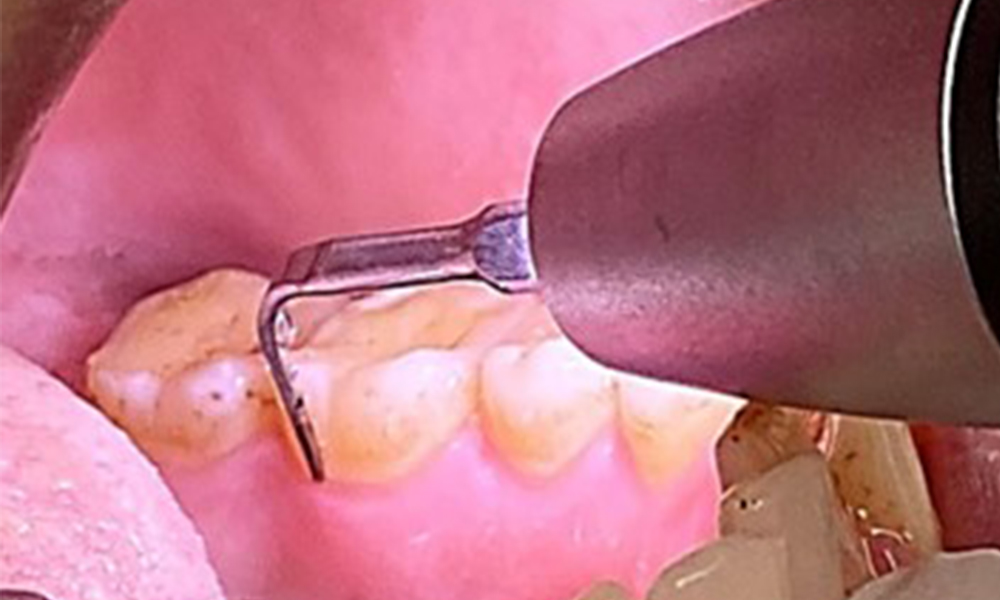

Целта е да се контролира рискът от заболяване чрез отстраняване на супрагингивалния и субгингивалния биофилм. Инструментите трябва да бъдат подбрани въз основа на нуждите на пациента. Първо трябва да се отстранят зъбният камък и всички конкременти с помощта на ултразвукови и/или ръчни инструменти (фиг. 10).